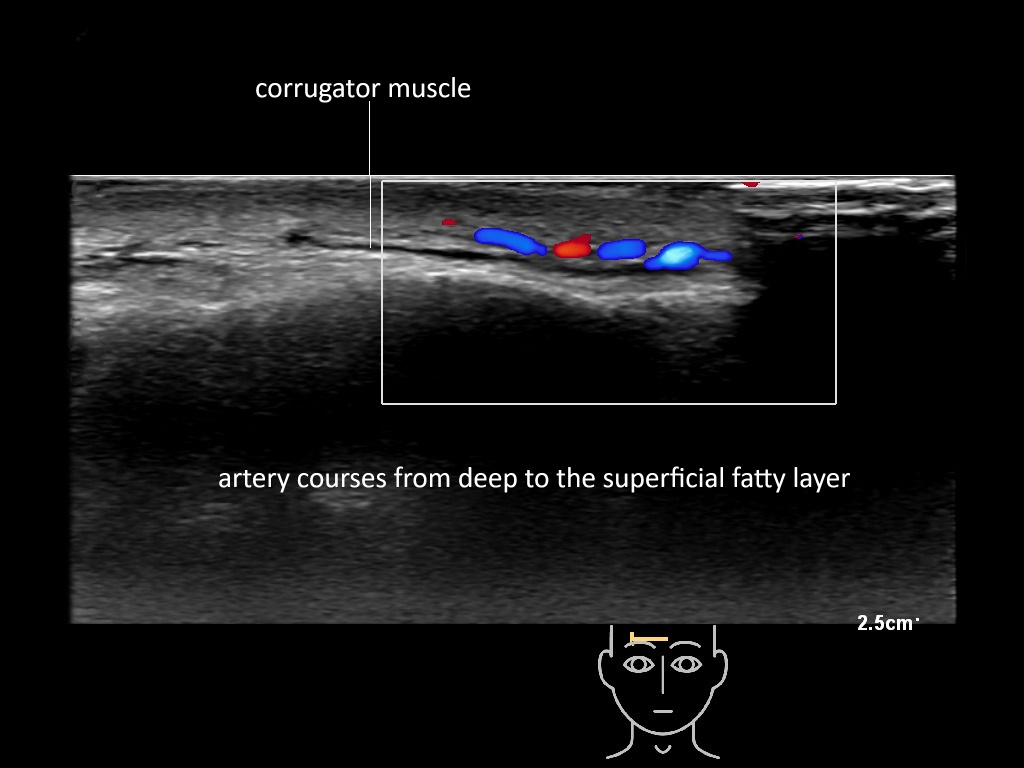

In this section you will learn more about the different layers of the face with the use of ultrasound. When you click on the secondary ultrasound image, you will see the different structures as an overlay. This will help to train yourself to recognize the different layers of the face.

Study the first image to recognize the different layers. If you are sure about the layers, swipe to the second image to view the answer (if applicable).